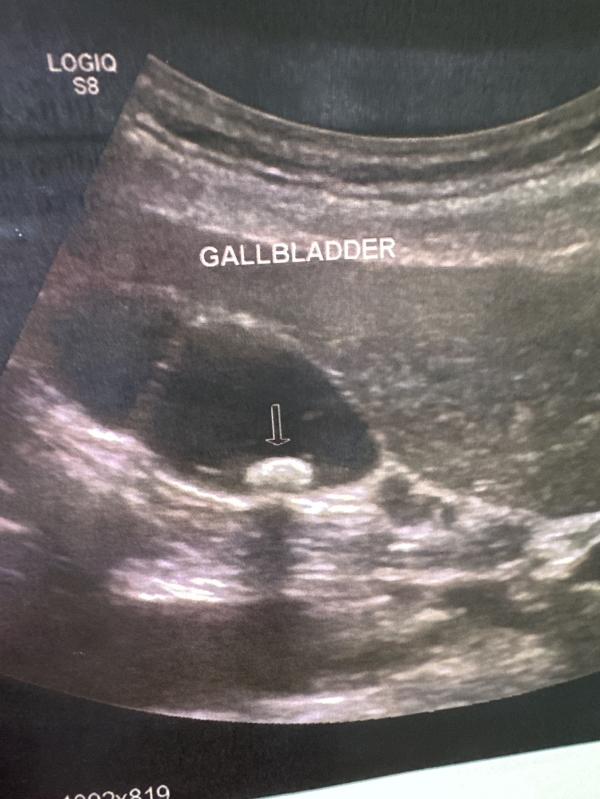

Девочки , особенно Воронеж, посоветуйте хорошего гастроэнтеролога . В желчном ( с перегибом) нашли камень 1 см. 4 месяца пила урсольфальк , но чет без изменений. У кого была подобная ситуация, что делали …Удаляли планово или ждали когда приспичит?

Все что свыше 1 см просит удаления в плановом порядке